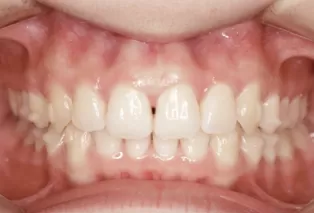

Photos intra-orales